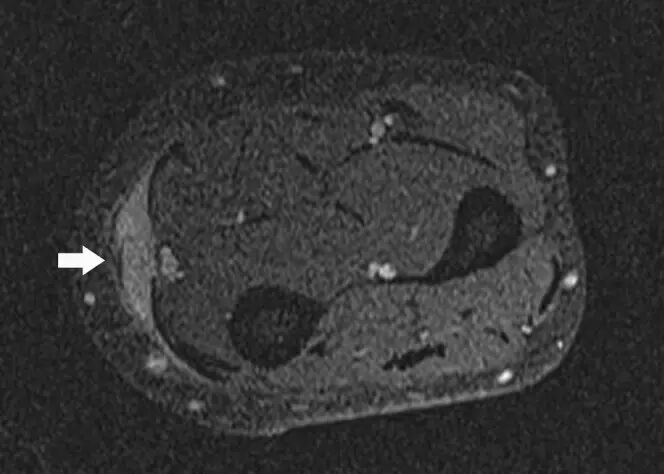

![]()

图26.一名78岁女性的平滑肌肉瘤患者出现右腿疼痛,肿胀和无法行走。 (a)通过小腿的轴向T1加权的MR图像显示在胫骨前部和胫骨后肌中主要为低信号强度的大的、小叶的、清晰分界的团块损伤(箭头)。团块延伸到皮下组织(箭头)。由于身体活动减少,胫骨后隔室中的肌肉显示突出的脂肪浸润(星号)。 (b)具有脂肪抑制的轴向T2加权MR图像显示具有低信号(空心箭头)的外周坏死区域的主要高信号强度(箭头)的肌内病变。在该脂肪抑制图像上,比较在胫骨后部(星号)中的低信号强度,脂肪替代肌肉的外观与部分(a)中的脂肪替代肌肉的外观。 (c)具有脂肪抑制的轴向T1加权MR图像显示包块的不均匀增强(箭头)。包块病变的活组织检查提示胫骨肌肉的平滑肌肉瘤。 T,胫骨。